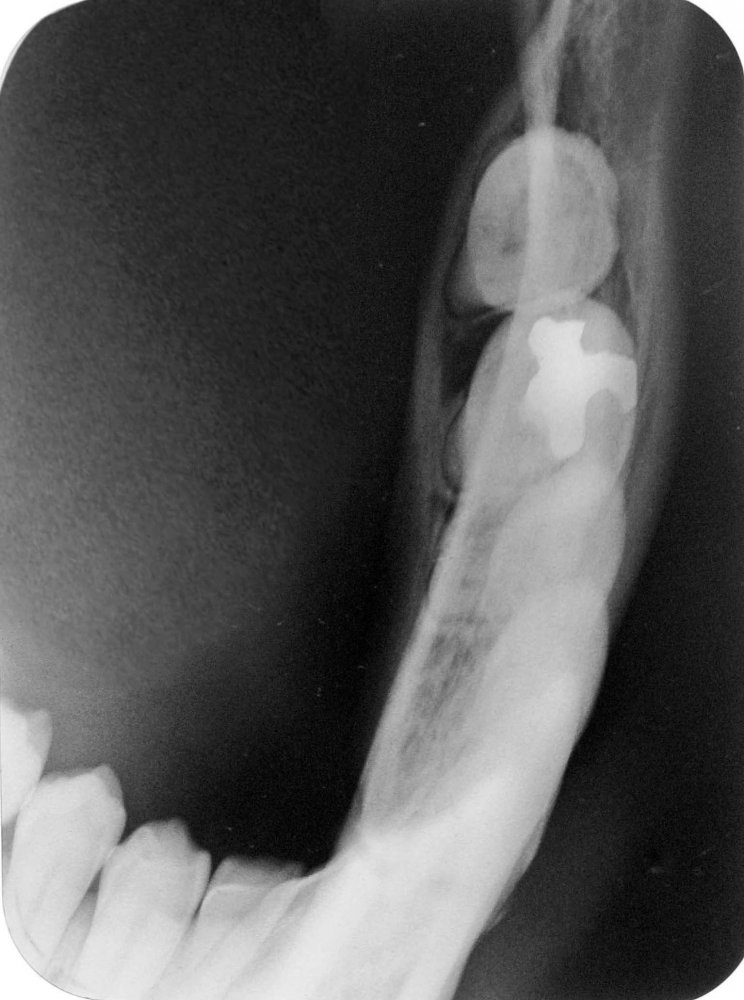

RX. Periapicales